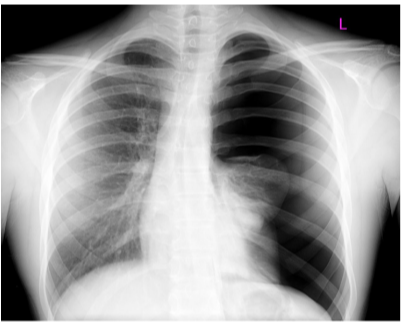

Lungs — general

Lie on either side of the mediastinum and surrounded by the pleural cavities

Air enters them via the main bronchi

Pulmonary arteries deliver deoxygenated blood to the lungs from the right ventricle, while oxygenated blood returns to the left atrium via the pulmonary veins

(contrary to “normal” functioning of veins & arteries).

Landmarks recognizable in the lung

The base —

Situated on the diaphragm

The apex —

Projects above rib 1 & into root of neck

Costal surface —

Adjacent to ribs + Intercostal spaces

Mediastinal surface —

Lies against mediastinum anteriorly & vertebral column posteriorly — this surface contains the hilum

3 borders —

Inferior border —

Sharp, separates the base from the costal surface

Anterior border —

Sharp, separates costal surface from medial surface

Posterior border —

Smooth & rounded, separates costal surface from medial surface

We can also recognize certain indentations corresponding to surrounding structures